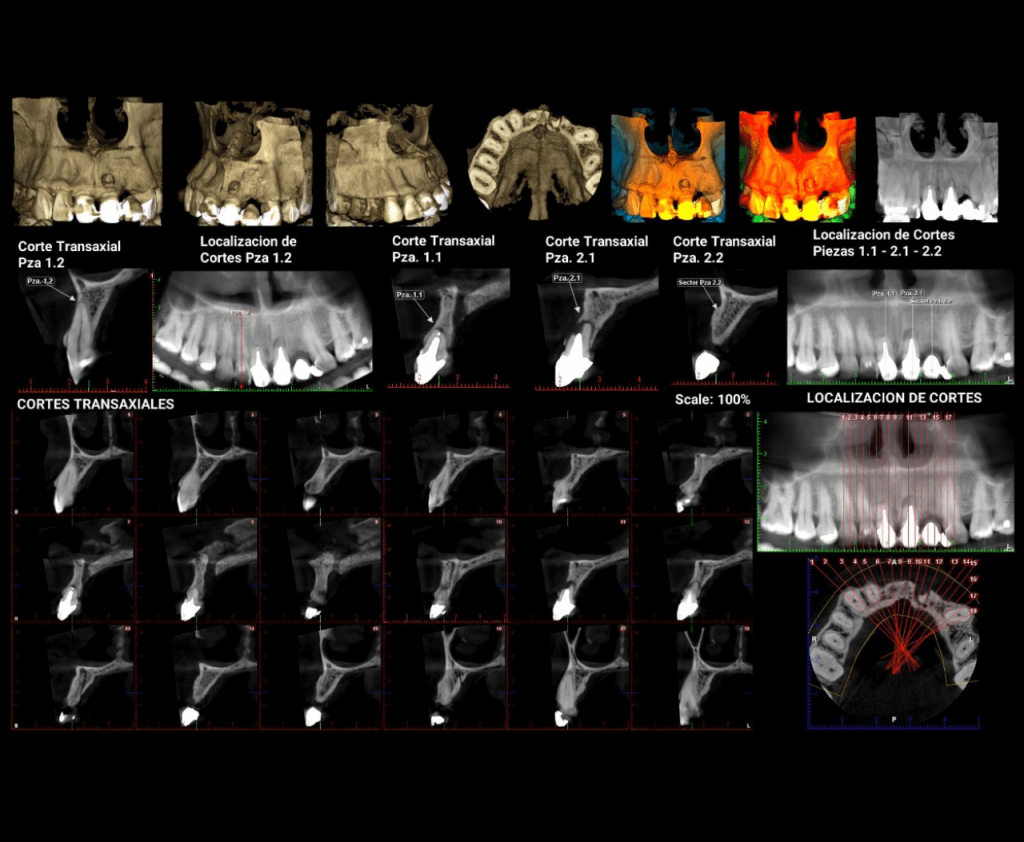

RADIOGRAFÍA Y TOMOGRAFÍA CONE BEAM ODONTOLÓGICA

CRYT Centro Radiológico y Tomográfico Odontológico / Dental en Salta